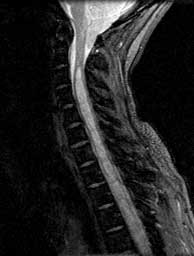

FSE T2 sagittals

Septated cavity with CSF signal extending form C3 to the conus. Peglike cerebellar tonsils herniated well below the foramen magnum.